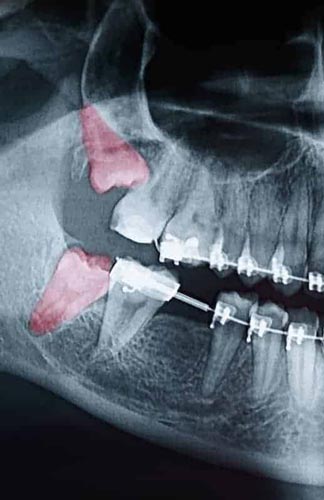

Wisdom teeth can begin to grow in sideways, only partially erupt, erupt in the wrong position, or get stuck beneath the gum and bone — called impacted teeth. Additional complications include:

We evaluate patients’ wisdom teeth before they start to come in, monitoring their formation and progress using X-rays. If the teeth show signs of causing complications, we suggest having them removed. Since early treatment is beneficial to patients, we recommend children be evaluated when they are in their mid-teens.